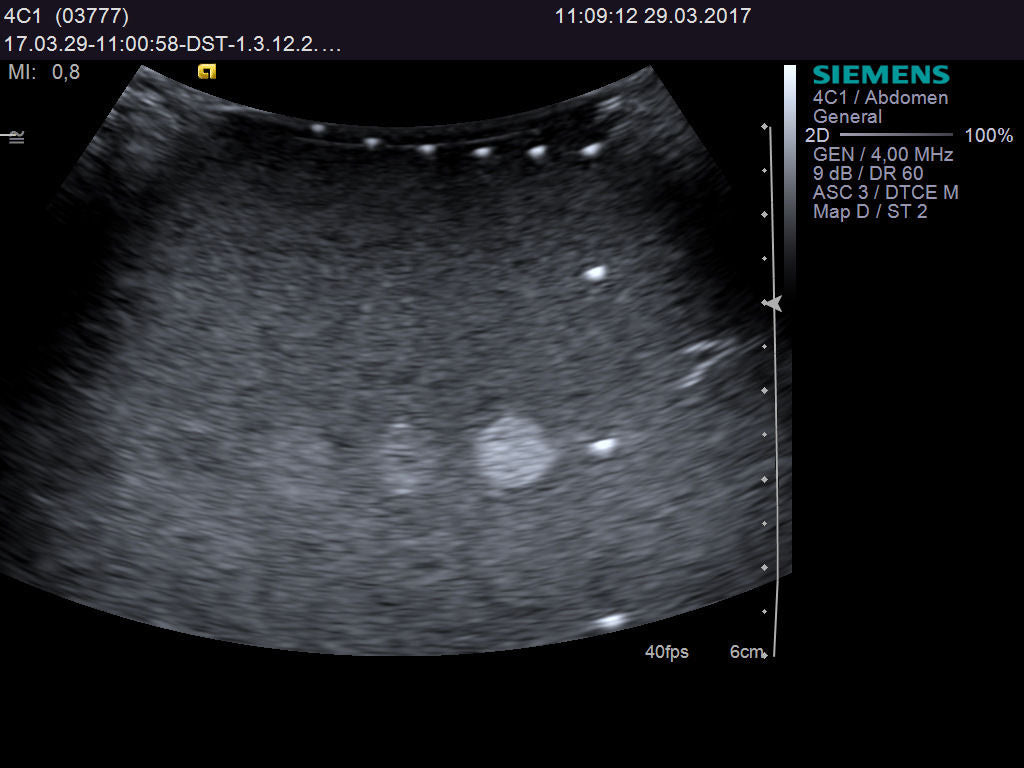

Understanding the Ultrasound Probe SIEMENS Acuson 4C1

The Ultrasound probe SIEMENS Acuson 4C1 employs cutting-edge imaging technology to provide high-resolution images that enhance diagnostic capabilities. It uses a linear array transducer, which allows it to capture detailed anatomical structures in real-time. This technology improves the clarity of the images, making it easier for healthcare professionals to identify and assess various conditions. Because of its advanced features, this probe is indispensable in ultrasound examinations.

This versatile ultrasound probe is suitable for a wide range of applications, including obstetrics, gynecology, and abdominal imaging. As a healthcare professional, you can rely on the Acuson 4C1 for both routine examinations and specialized procedures. The probe's design also ensures patient comfort during scans, which is crucial during sensitive examinations. Hence, it is widely used in hospitals and clinics around the world.